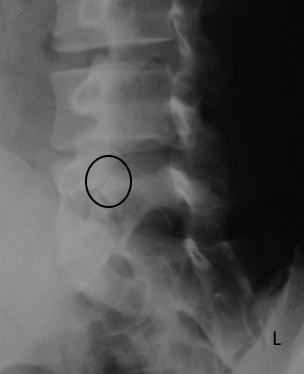

This radiographic appearance demonstrates spondylolysis on oblique lumbar spine images

What is the "broken neck of the Scotty dog"-pars interarticularis?